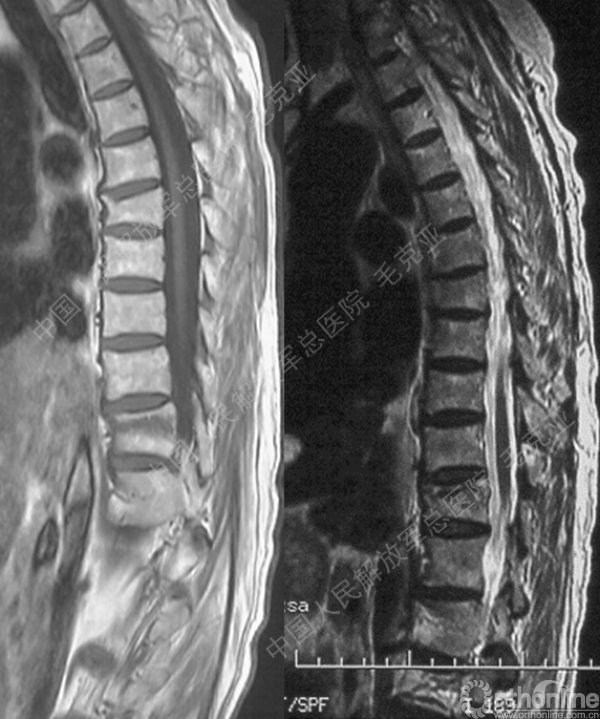

导语:随着社会老龄化的不断加速,骨质疏松性椎体压缩骨折作为一种普遍存在的老年骨科疾病已经成为现今骨科界的一个热点话题。传统的保守疗法治疗效果不佳,而现有的椎体增强技术又具有多种风险和缺陷。针对这种现状,中国人民解放军总医院毛克亚教授提供了一种新的解决方法。